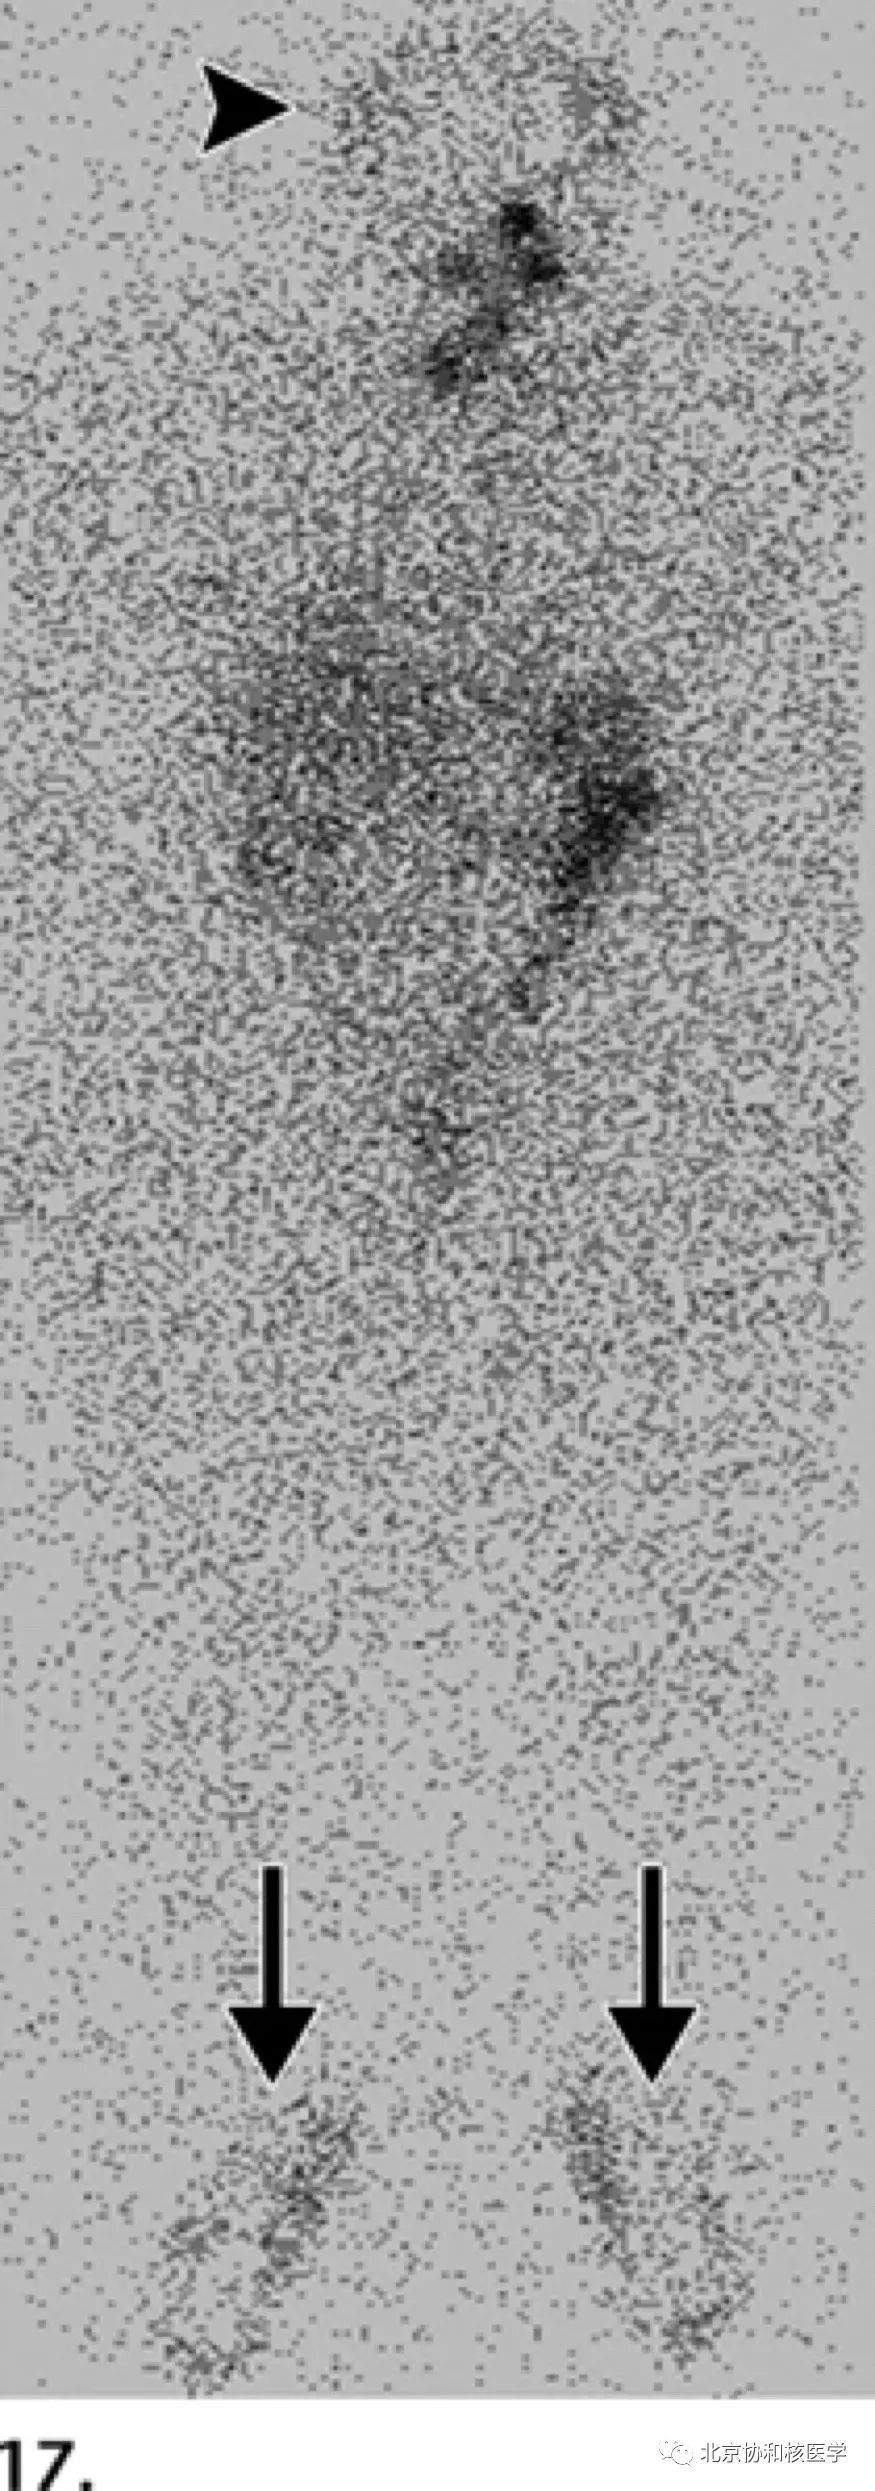

鼻骨骨样骨瘤所致碘摄取,腹部另可见由于巨大肾囊肿所致碘异常摄取: